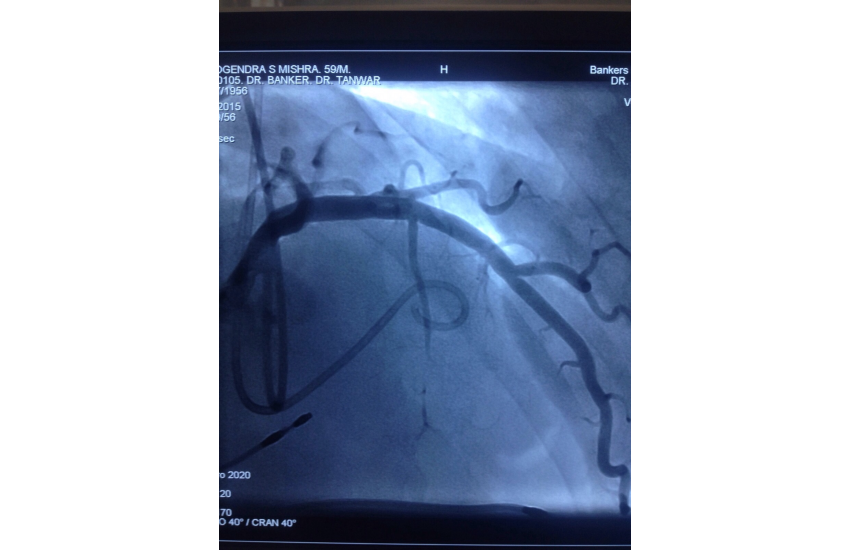

CAG revealed normal coronaries,holter shows sinus bradycardia,RBBB with LAHB,intermittent AF, TMT shows blunted chronotropic response and hypotensive response so he has been planned for PPI with back up of pacemaker patient treated with beta blockers and corderone,after 7 days of PPI,he has undergone alcohol septal ablation successfully,prior his dynaemic gradient was 50 mmhg in rest n 80 mmhg with exercise which reduced to 20mmhg after procedure. Now patient is under close follow up so will continue updating.